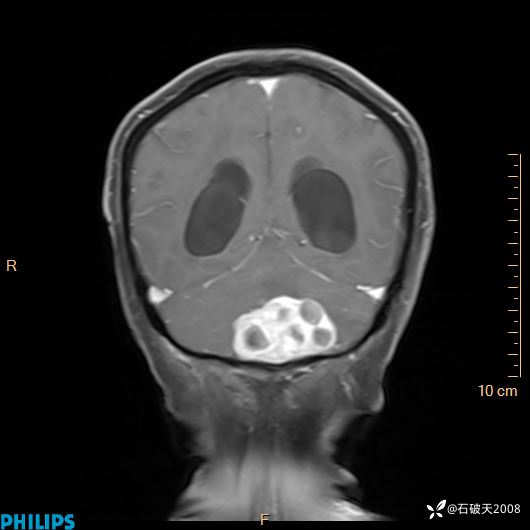

书上说这个肿瘤发生在幕下仅4.09%,你会想到它吗?(病理已公布)

增强冠状位